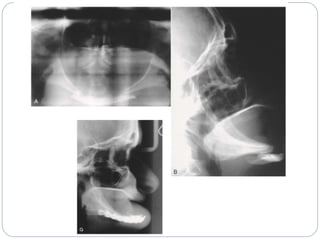

‫رادیوگرافیک‬ ‫ارزیابی‬

‫گرافی‬ ‫انواع‬

‫پانورامیک‬

‫اسکال‬ ‫لترال‬ ‫و‬ ‫سفال‬ ‫لترال‬

‫مندیبول‬ ‫ابلیک‬ ‫گرافی‬

PA‫اسکال‬

‫واترز‬ ‫گرافی‬

‫گرافی‬SMV

‫کالدول‬ ‫گرافی‬

‫معکوس‬ ‫تاون‬ ‫و‬ ‫تاون‬ ‫گرافی‬

‫آگزیال‬ ‫و‬ ‫کرونال‬ ‫و‬ ‫ساژیتال‬ ‫مقطع‬ ‫با‬ ‫اسکن‬ ‫تی‬ ‫سی‬

‫اسکن‬ ‫تی‬ ‫سی‬ ‫بعدی‬ ‫سه‬ ‫بازسازی‬